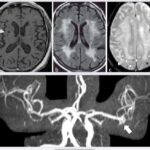

Si le cerveau des hommes est en moyenne plus grand de 10% en moyenne 1,350 kg que celui des femmes 1,200 kg, ces différences de taille n’ont pas d’impact sur les capacités intellectuelles.

Les études révèlent des variations dans les volumes de matière grise et blanche entre les sexes, avec plus de substance grise chez la femme et plus de blanche chez l’homme mais cela disparaît si on compare des cerveaux de même volume.